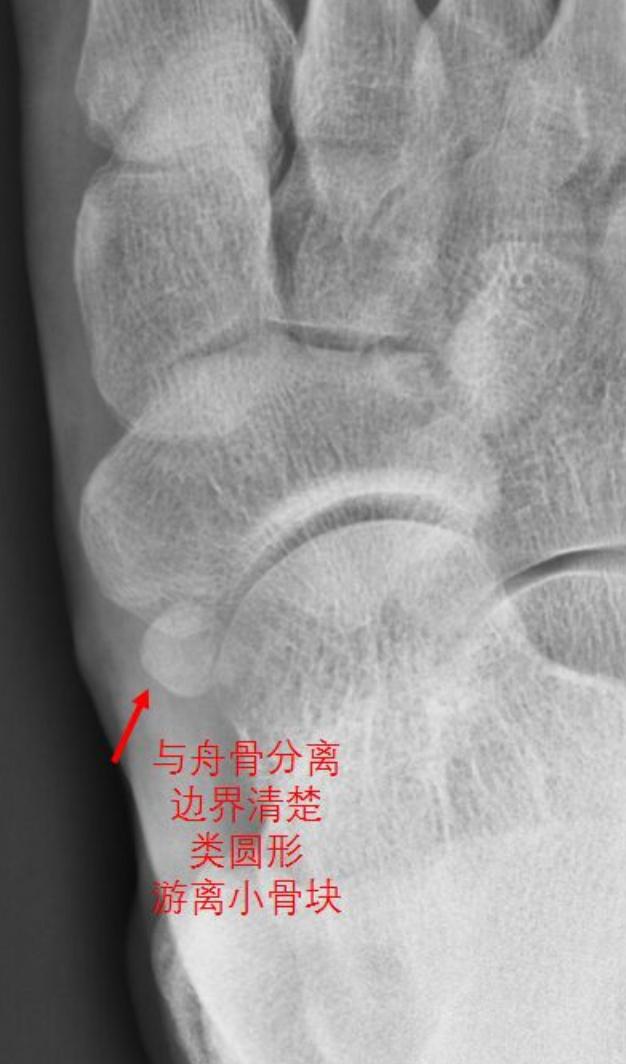

I型:籽骨型,在X线上表现与舟骨分离的类圆形或椭圆形小骨块,局部很少触及骨性隆起,患者多无肿痛等临床症状。